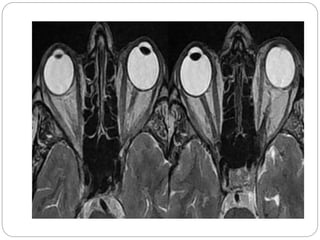

 About 30 percent of people with Graves' disease show

some signs and symptoms of a condition known as

Graves' ophthalmopathy. In Graves' ophthalmopathy,

inflammation and other immune system events affect

muscles and other tissues around your eyes. The

resulting signs and symptoms may include:

 Bulging eyes (exophthalmos)

 Graves' ophthalmopathy About 30 percent of people with Graves' disease show some signs and symptoms of a condition known as Graves' ophthalmopathy. In Graves' ophthalmopathy, inflammation and other immune system events affect muscles and other tissues around your eyes. The resulting signs and symptoms may include:  Bulging eyes (exophthalmos)  Gritty sensation in the eyes  Pressure or pain in the eyes  Puffy or retracted eyelids  Reddened or inflamed eyes  Light sensitivity  Double vision  Vision loss